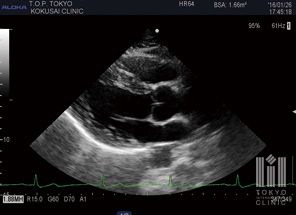

心臓超音波検査

冠動脈CTとMCG検査(心筋虚血診断検査)を併用することで、心疾患を早期に発見します。